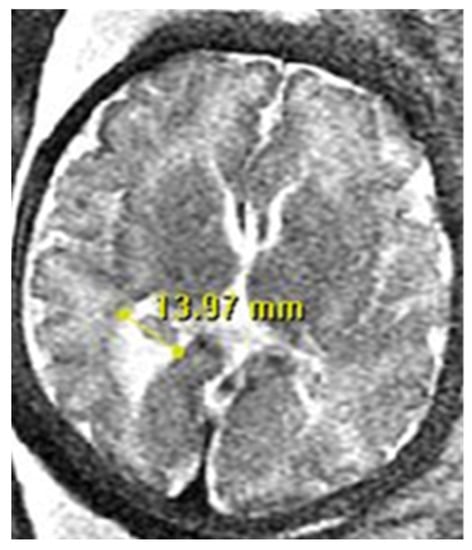

There are specific requirements that must be met when measuring the size of the lateral ventricle. It is to be measured in the axial plane, in the thalamic section, at the level of the atrium, and at the posterior margin of the glomus of the choroid plexus (Figure 1).

Figure 1. Neuroradiologists’ criteria for measuring the lateral ventricle in Fetal Brain MRI: Lateral ventricular measurement is measured at the level of the atrium at the posterior margin of the glomus of the choroid plexus, on the axial plane through the thalamus.